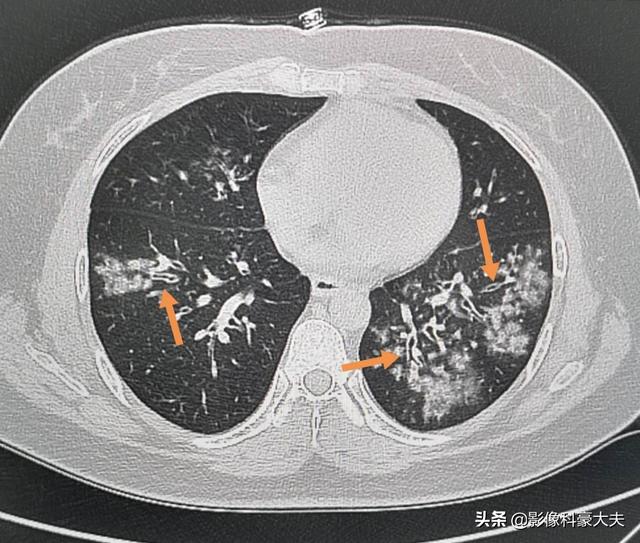

この若い女性のように、咳と発熱があり、痰はほとんど出ず、風邪薬やインフルエンザの薬を飲んでもよくなかった。CTを撮ったところ複数の小さな気道壁肥厚を伴う両肺の斑状炎症と気道内の病巣の中心分布は、新生肺炎ではなくマイコプラズマ肺炎と一致する。